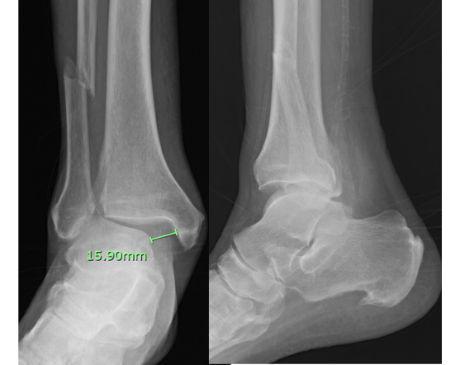

I was hit by car, had a compound fracture with a bone sticking out of my left foot. Broken tibia and fibia?. Screwed plate and bones back together. I am healing fine, next visit 3/26 to remove stiches. I seem to have total function of foot. Still have 2 more weeks of not using leg, but very hopeful.